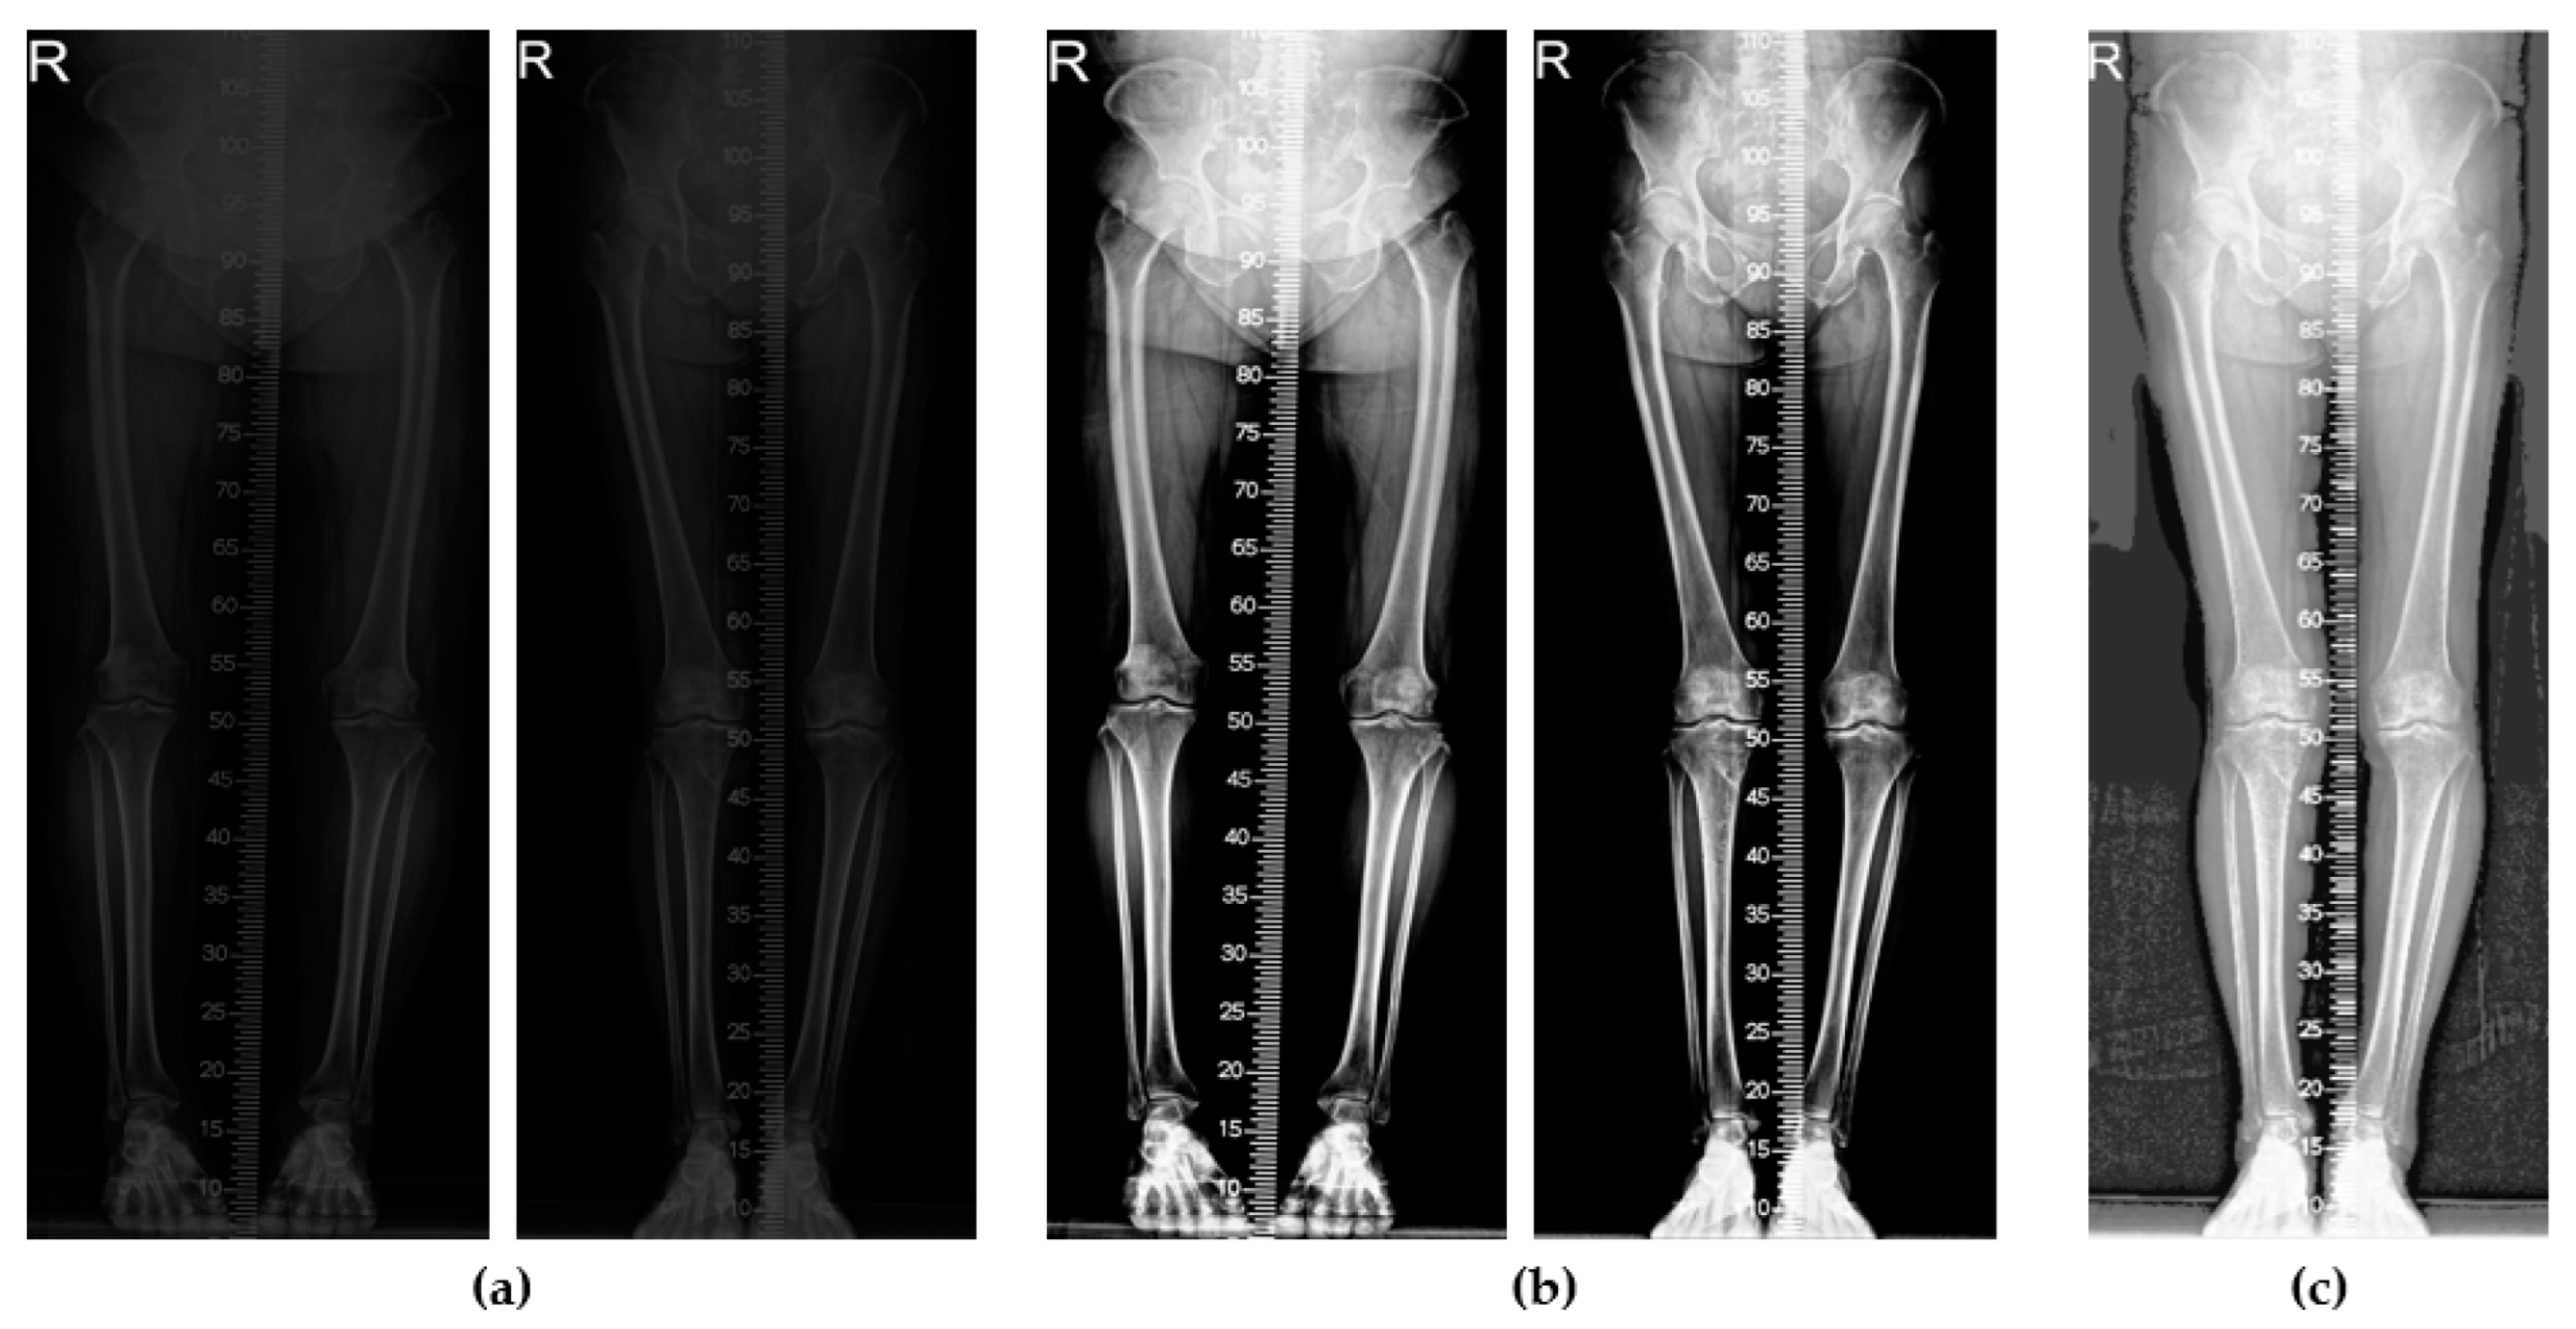

2.2. Image Preprocessing

2.3.1. Femur and Tibia Segmentation